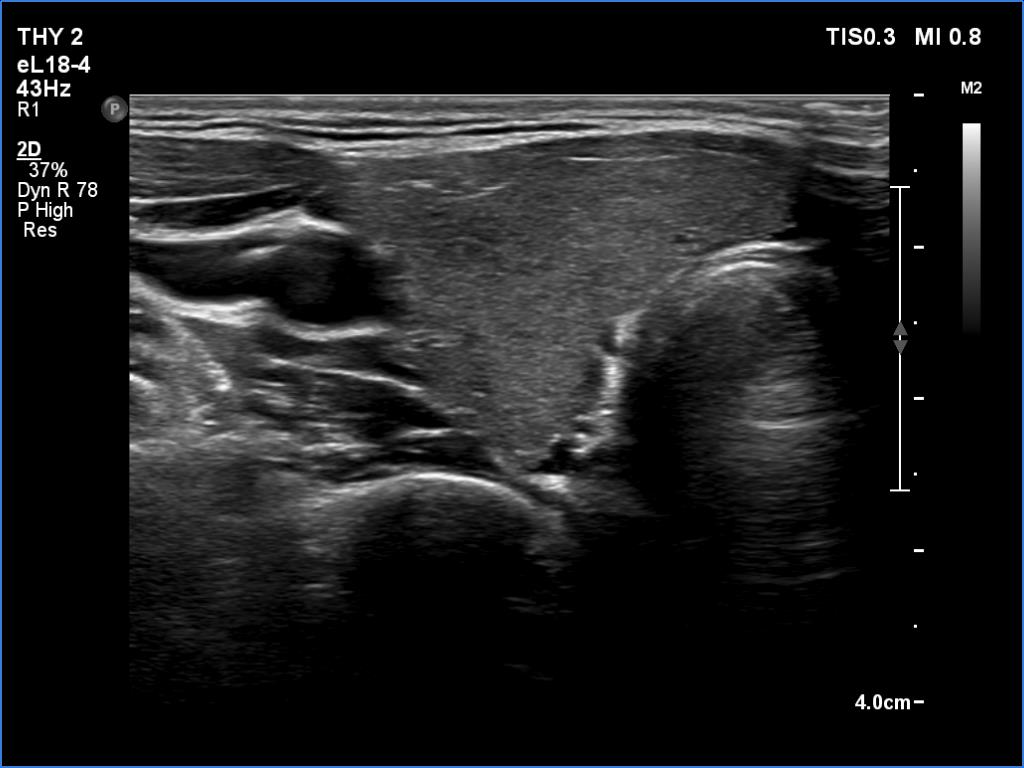

Left lobe, transverse scan

This is the usual course of Graves' disease regarding the change in echo pattern - before, during and after the activity of the autoimmune process. The only exception is the change in the size of the thyroid. In most cases, the thyroid increases during the activity of the disease, then returns to normal. However, in this patient the age counts: at the first examination, the patient was only 15-year-old.

- There are two situations in Graves 'disease where circulation is increased. At the stage of disease activity and when hypothyroidism is observed with medication. In the former case, the blood flow is almost always increased, in the latter it can be decreased and increased.